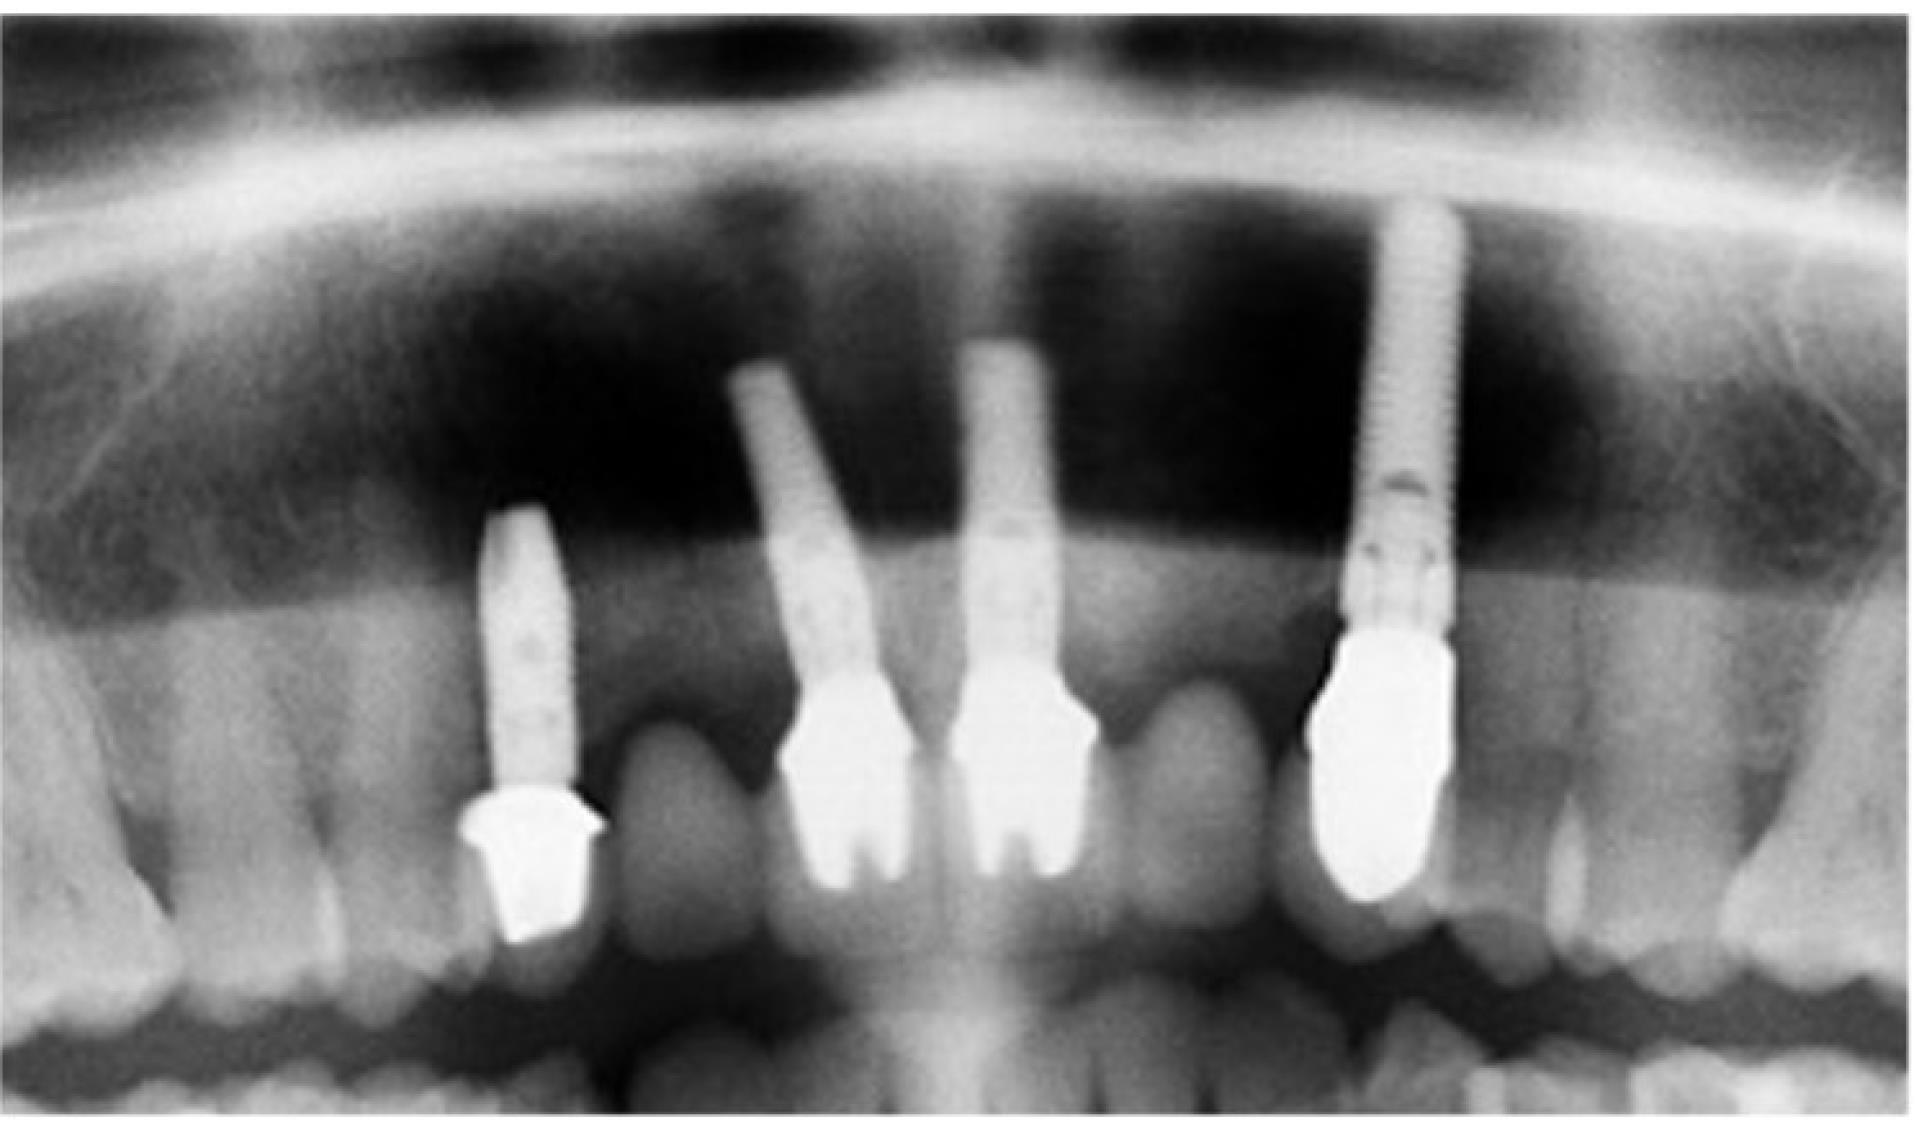

Final restoration

After 4‒6 months, the osseointegration and maturation of the gingival flap were completely developed. The soft tissue contour around the dental implant was corrected by fabricating the old provisional crown or making a new crown, considering the desired result. A digital protocol was routinely used to fabricate provisional transocclusal crowns based on dental implants. The provisional crown was used to facilitate processing and control the pressure force. The criterion for proper pressure on the mucosa during profiling was the presence of mild ischemia, which resolved after 10‒15 minutes. If ischemia persisted, the volume of the provisional crown was corrected to achieve the desired effect. After the final shape of the gingival profile was formed around the implant, a final prosthesis was fabricated. Both digital and analog techniques were used to fabricate final crowns. The impression copings or scan markers were individualized by copying the soft tissue contour onto them immediately after removing the provisional crown with a liquid composite. In the classic variant of fabricating provisional structures, a combination of an individualized zirconia abutment and a ceramic crown was used. The type of ceramic crown was selected depending on each patient’s occlusal and esthetic characteristics (Figures 7, 8, 9, and 10).

Figure 9.

initial panoramic image

Bone resorption after 12 months

A slight bone resorption was detected in the distal papillae. The average distance between the implant shoulder and the first contact of the bone with the implant was 1.05 ± 0.3 mm after 12 months. In the projection of the mesial papilla, the parameter was 0.96 ± 0.5 mm.